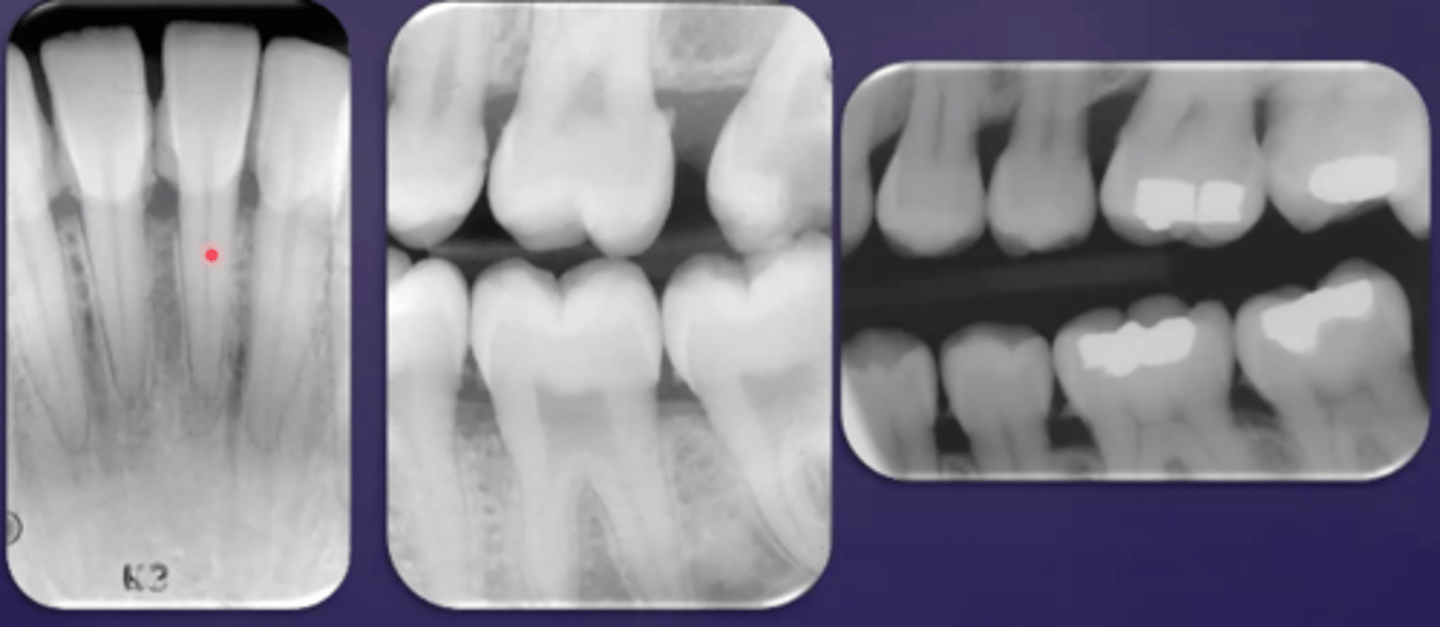

overlapped contacts

contacts are overlapped

central ray not directly through the interproximal spaces

foreshortened images

teeth appear short with blunted roots

caused by too steep vertical angulation

elongated images

teeth appear long and distorted

vertical angulation too flat

incorrect placement of premolar bite wing

distal surfaces of the canine are not visible of the image

receptor too far back

make sure anterior edge of receptor is at the midline of the mandibular canine

incorrect placement of molar bite wing

third molar regions not visible on the image

receptor too far forward

make sure anterior edge of the receptor is at the midline of the mandibular second premolar

center the molar bite wing over the mandibular second molar